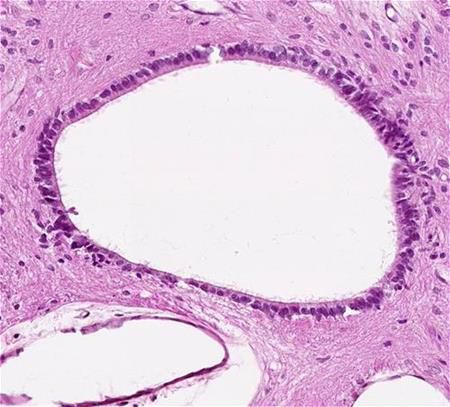

Epithelium of stomach surface

Stomach

Epithelium

Surface

simple columnar